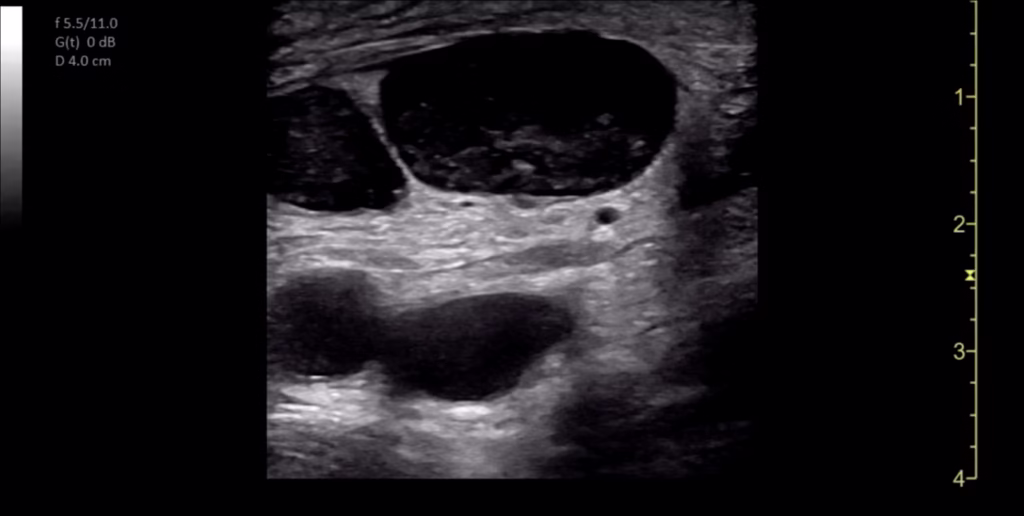

POCUS of the skin and soft tissues was performed by a board-certified pediatric emergency medicine attending with emergency ultrasound fellowship training on a GE Venue machine (Waukesha, WI, USA), using a 4.2-13.0 MHz linear probe in a musculoskeletal preset. The POCUS examination revealed multiple bilateral hypoechoic ovoid structures with no identifiable hilum, the largest of which measured 1.9 cm in diameter (Figure 2). There was also markedly increased internal vascularity in a “fire-like” distribution within all the involved structures on color Doppler (Figure 3). Additionally, the POCUS examination demonstrated posterior acoustic enhancement, increased echogenicity of the surrounding soft tissue, and superficial cobblestoning (Figure 4). These POCUS findings, along with the notable absence of gut signature, internal heterogeneity, or free fluid, facilitated the identification of lymphadenopathy. The presence of posterior acoustic enhancement, increased echogenicity of surrounding soft tissues, and increased vascularity on color Doppler, in combination with physical examination findings of tenderness, warmth, and overlying erythema, were suggestive of infectious lymphadenitis with surrounding cellulitis.

Figure 2. Point of care ultrasound (POCUS) of right inguinal region. Multiple enlarged lymph nodes superficial to the femoral artery and vein.

Ultrasound has been suggested as the first-line imaging modality for evaluating lymphadenopathy due to its rapid image acquisition and interpretation, lack of ionizing radiation, and low cost [7]. Normal lymph nodes are typically described as well-defined ovoid structures with hypoechoic parenchyma, an echogenic hilum, and hilar vascularity on Doppler imaging (Figures 6 and 7) [3]. Additional sonographic features, such as the presence of posterior acoustic enhancement, increased echogenicity of adjacent soft tissues, and specific color Doppler patterns, can aid in differentiating reactive, infectious, and malignant lymphadenopathy (Table 2) [3,4]. In this case, multiple hypoechoic ovoid structures without an identifiable hilum were visualized. Additionally, posterior acoustic enhancement, adjacent soft tissue edema, and an enhanced color Doppler signal were all present. The combination of hypoechoic echotexture, posterior acoustic enhancement, and the absence of an identifiable hilum likely represented liquefaction. Intranodal liquefaction is suggestive of necrosis and can help distinguish pathologic etiologies (Table 2) [3,4,8].

Sonographic features of lymphadenopathy due to CSD have been previously described in the literature. García et al. reported the ultrasonographic findings in 47 patients diagnosed with CSD who underwent a radiology-performed skin and soft tissue ultrasound [4]. They noted multiple findings that were present in a majority of patients in the series, including the presence of three or more enlarged lymph nodes (91%), hypoechoic echotexture (100%), posterior acoustic enhancement (89%), and increased echogenicity of surrounding soft tissues (100%) [4]. The POCUS examination that was performed in our case demonstrated each of these characteristic findings. Additionally, all 21 cases in the García et al. series that were evaluated with color Doppler demonstrated “highly vascularized lymph nodes” with a loss of the typical vascular architecture. García et al. coined the term “fire pattern” to describe the diffuse color Doppler signal observed within the enlarged lymph nodes and postulated that this pattern was due to neovascularization associated with Bartonella infection [4]. We observed a similar distribution of Doppler signal in our case (Figure 3).